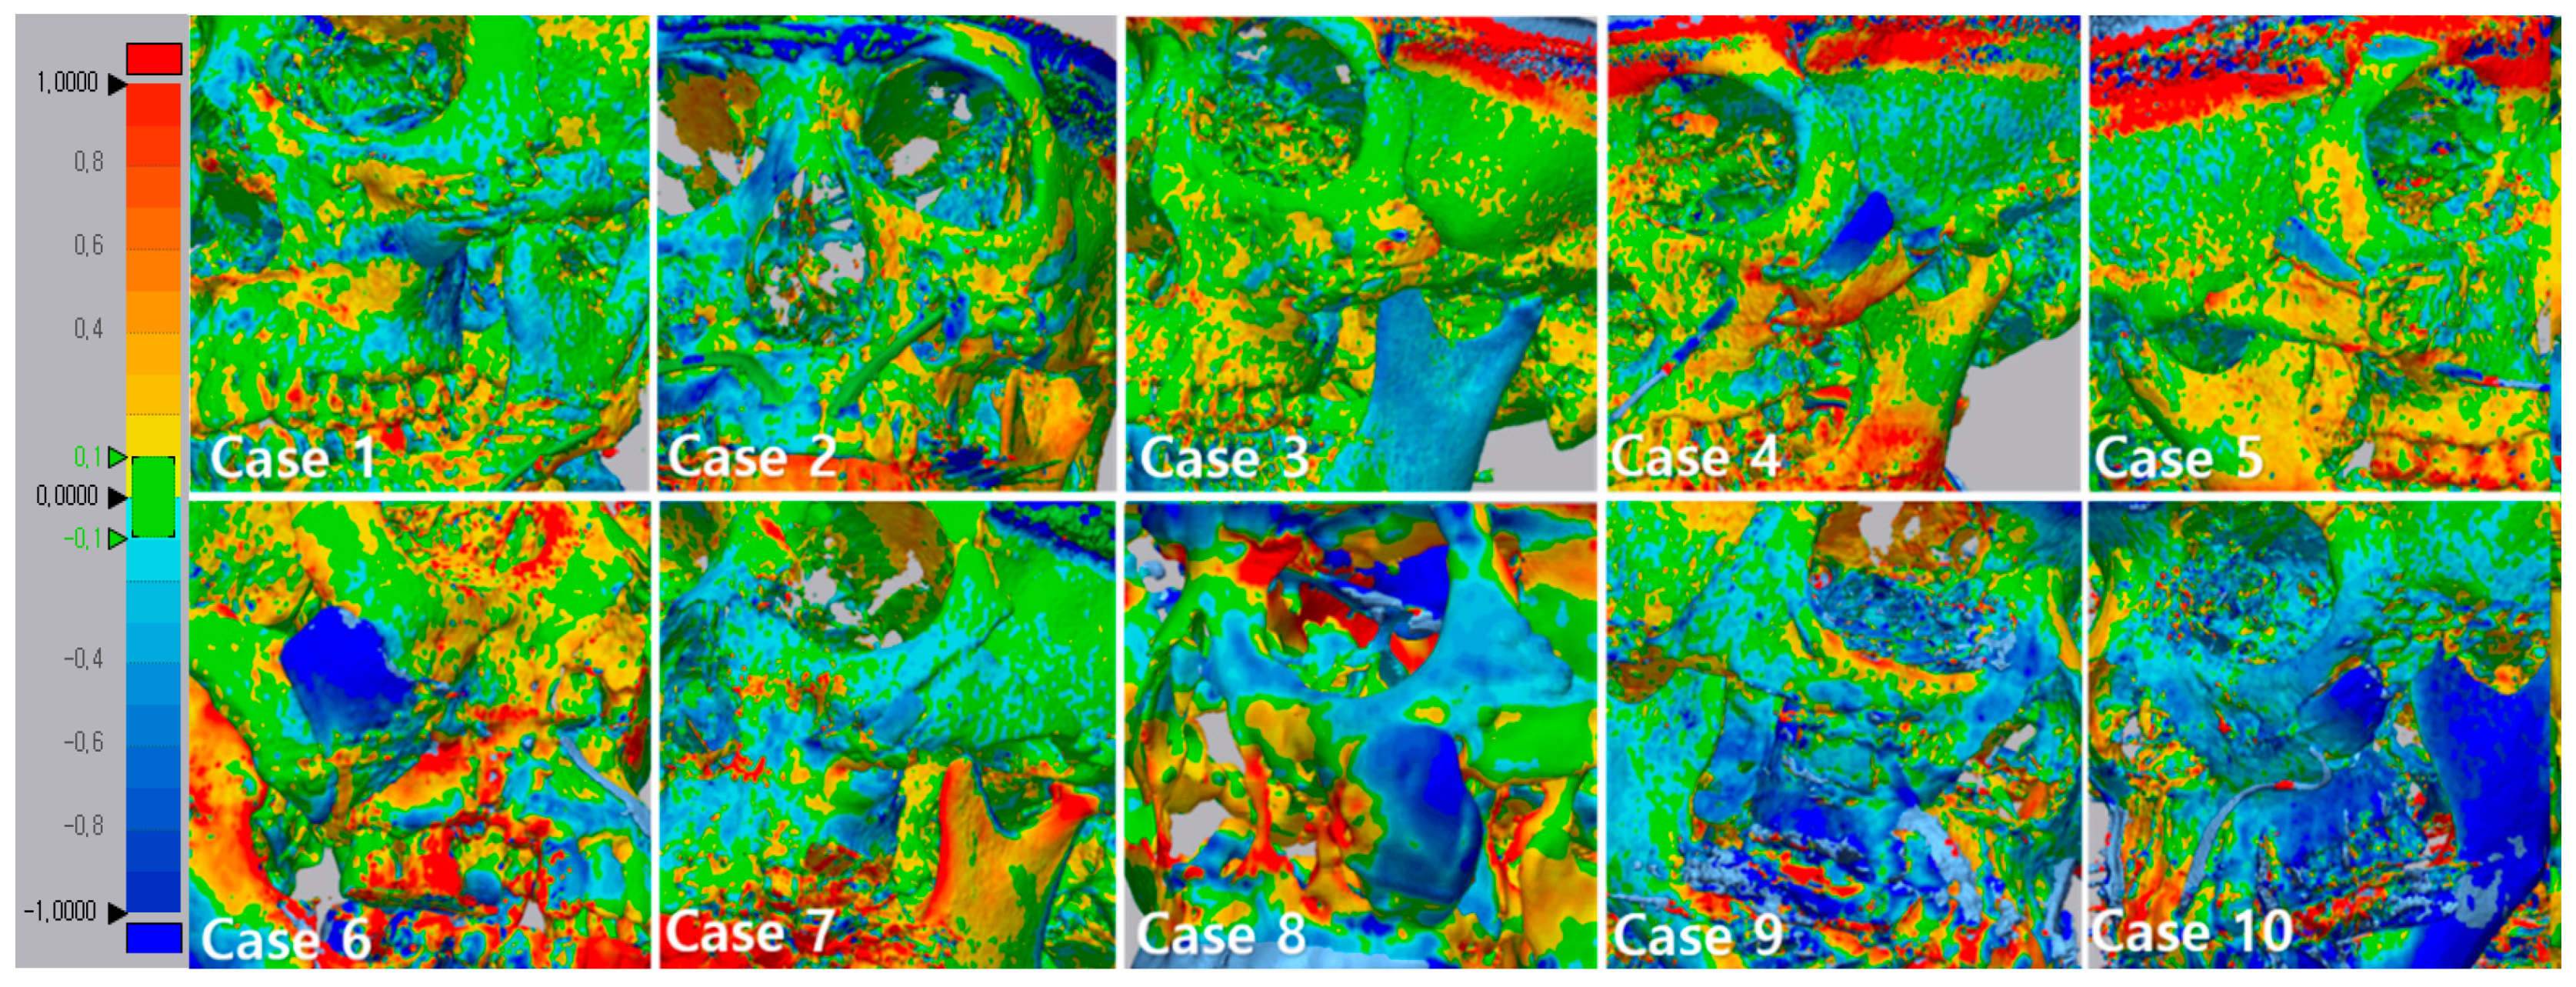

3.3. 3D Comparison between Immediate Post Operative and 6 Months Post Operative

| Point 1 | 2 | 3 | 4 | 5 | 6 | 7 | 8 | 9 | 10 | Aver. | SD | |

|---|---|---|---|---|---|---|---|---|---|---|---|---|

| Case 1 | 0.3853 | 0.3461 | 0.5375 | 0.3455 | 0.4526 | 0.233 | 0.1499 | 0.1982 | 0.0476 | 0.0812 | 0.2776 | 0.1616 |

| 2 | 0.1469 | 0.3044 | 0.0014 | 0.2874 | 0.0191 | 0.1403 | 0.0927 | 0.0263 | 0.0695 | 0.0675 | 0.1155 | 0.1064 |

| 3 | 0.0979 | 0.0137 | 0.1259 | 0.0966 | 0.0821 | 0.1918 | 0.2396 | 0.3076 | 0.2452 | 0.3689 | 0.1741 | 0.1170 |

| 4 | 0.3342 | 0.0045 | 0.0888 | 0.2472 | 0.6319 | 0.6853 | 0.6889 | 0.6646 | 0.871 | 0.9915 | 0.5207 | 0.3327 |

| 5 | 0.1479 | 0.3236 | 0.1486 | 0.1077 | 0.4406 | 0.1422 | 0.5004 | 0.4437 | 0.5019 | 0.2645 | 0.3021 | 0.1602 |

| 6 | 0.4378 | 0.3892 | 0.337 | 0.3052 | 0.8668 | 0.7413 | 1.2819 | 1.4485 | 1.4251 | 1.6551 | 0.8887 | 0.5231 |

| 7 | 0.4298 | 0.2216 | 0.3879 | 0.2224 | 0.2695 | 0.2097 | 0.4689 | 0.3944 | 0.1436 | 0.456 | 0.3203 | 0.1192 |

| 8 | 0.4187 | 0.3392 | 0.5911 | 0.8404 | 0.5219 | 0.7681 | 0.7887 | 0.2335 | 0.1735 | 0.011 | 0.4686 | 0.2826 |

| 9 | 0.3199 | 0.1057 | 0.2524 | 0.1483 | 0.2272 | 0.3322 | 0.1833 | 0.4457 | 0.0755 | 0.045 | 0.2135 | 0.1270 |

| 10 | 0.3489 | 0.2618 | 0.9525 | 0.4041 | 0.288 | 1.3645 | 1.1981 | 0.6722 | 1.8174 | 1.3628 | 0.8670 | 0.5513 |